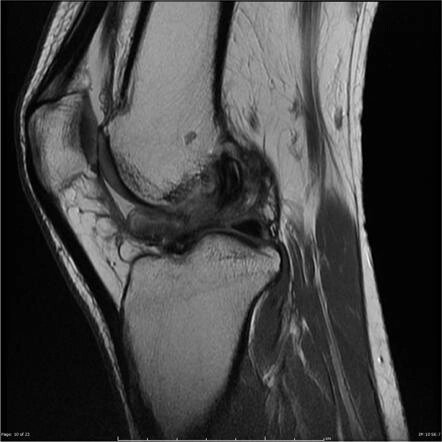

МРТ также позволяет определить положение большеберцового канала и выявить наличие рубцовой ткани кпереди от ПКС, которая обычно имеет низкую интенсивность сигнала.